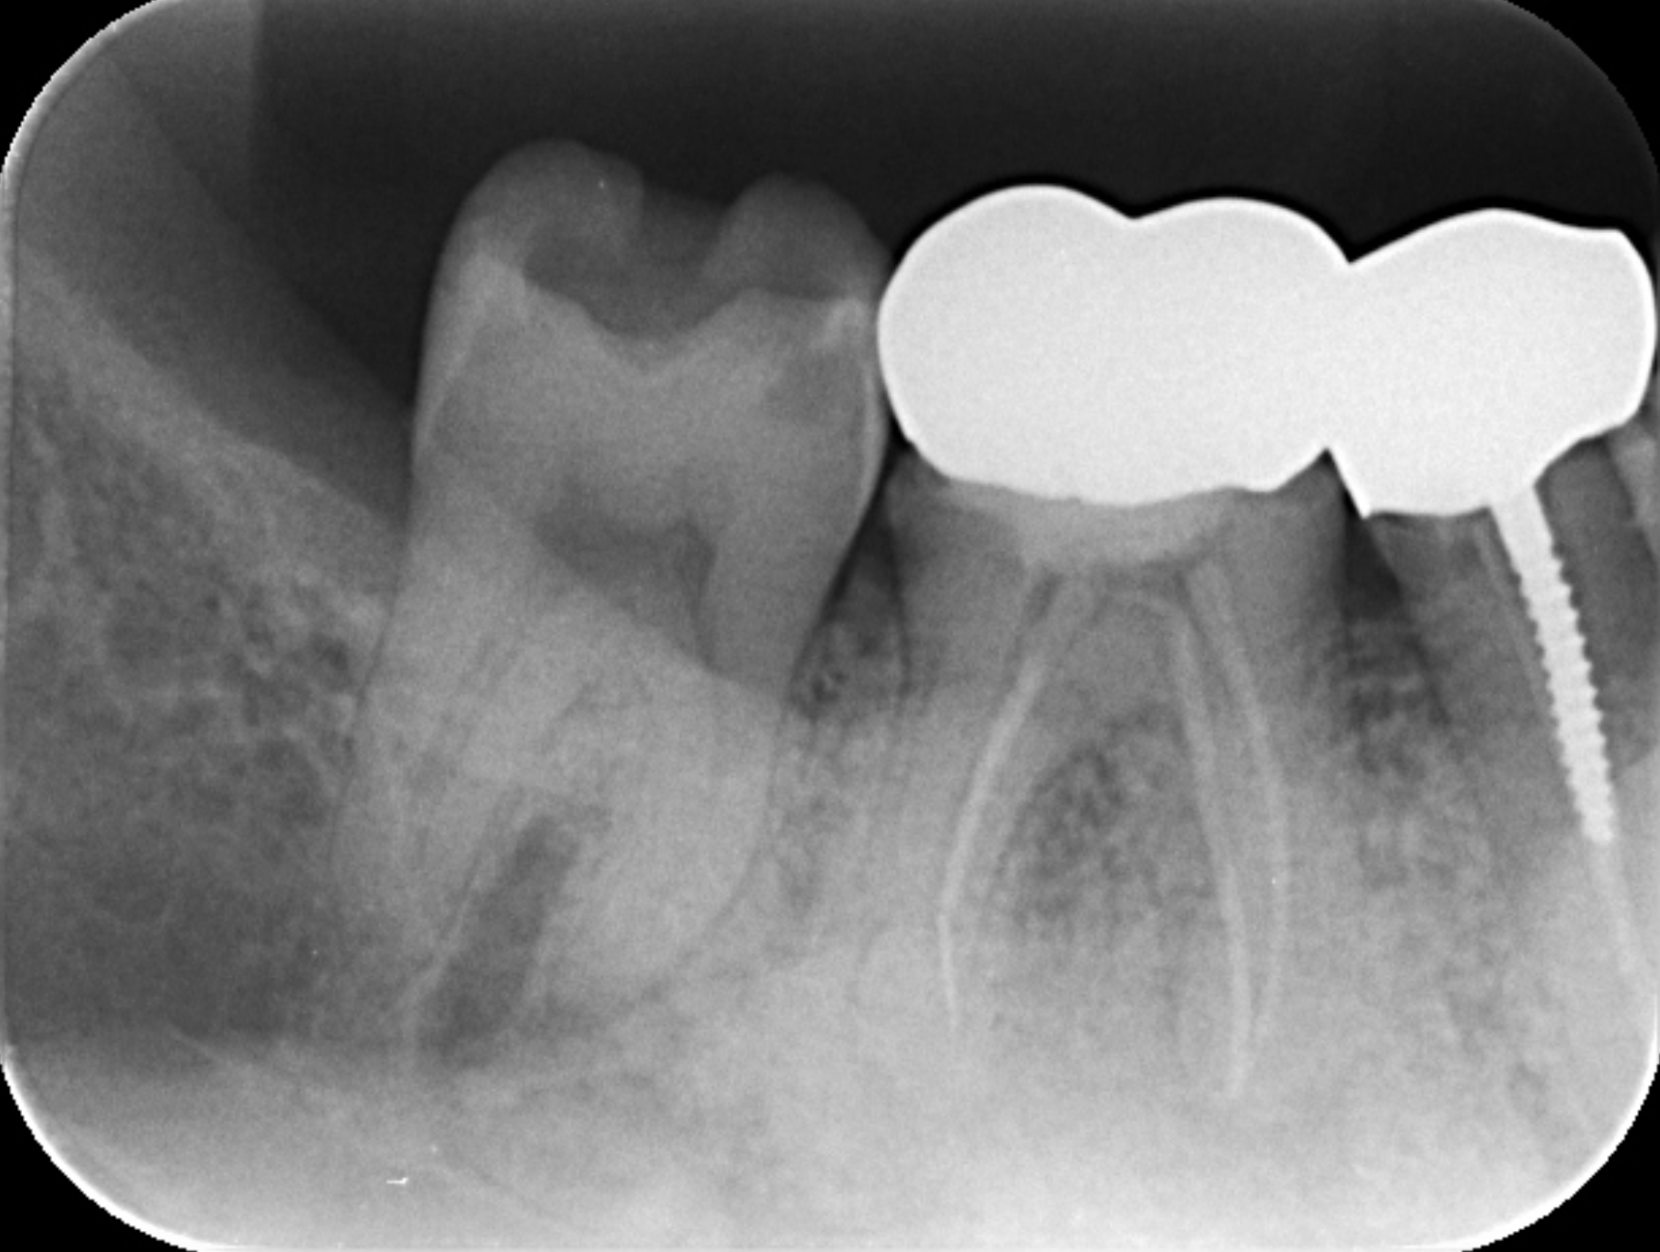

①失活による根管治療を行った

②術前CTによる根尖部の未治療および根尖透過像

| 診断 | 右下6.7根尖性歯周炎 | ||||

| 処置内容 (または主訴) | マイクロスコープ治療を用いた感染根管治療 | ||||